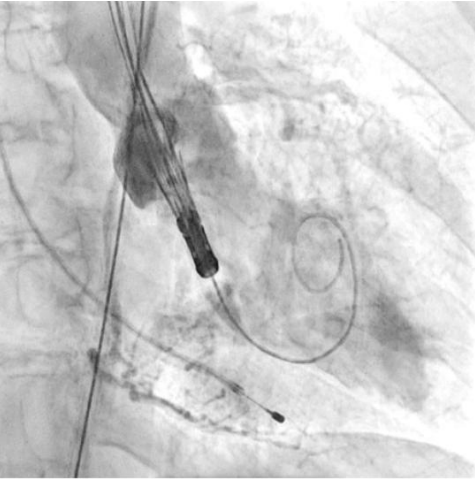

Процедура ТИАК выполнялась по стандартной методике, принятой в нашем центре (рис. 6-9). После предилатации баллонным катетером "Valver" 18×40 мм возникло ухудшение гемодинамики за счет развития выраженной аортальной регургитации, проявившееся снижением диастолического АД до 20 мм рт.ст. В срочном порядке была выполнена имплантация "Acurate Neo2 S" диаметром 23 мм в аортальную позицию, после чего явления гипотонии и сердечной недостаточности были компенсированы. Коронарные артерии не были скомпрометированы. После выполнения основного этапа операции интродьюсер из правой общей бедренной артерии удален, затем выполнено ушивание места доступа системой зашивающего устройства "ProGlide" (6F) и AngioSeal VIP (6F), наложен кожный шов. Ход оперативного лечения без особенностей.

Рис. 6. Пациентка В. Ангиография корня аорты: визуализируется минимальная регургитация.

Рис. 7. Пациентка В. Баллонная предилатация.

Рис. 8. Пациентка В. В момент проведения и позиционирования искусственного клапана визуализируется умеренная регургитация.

Рис. 9. Пациентка В. Контрольная ангиография.

Во втором клиническом случае был учтен предыдущий опыт и изменена тактика проведения вмешательства у пациентки с аналогичным фенотипом ЛЖ. Исключение этапа баллонной вальвулопластики способствовало снижению риска перегрузки ЛЖ за счет аортальной регургитации. Таким образом, на всех этапах операции у второй пациентки сохранялась разграничительная функция нативного клапана или биопротеза. В третьем клиническом случае у пациентки наблюдался массивный кальциноз АК, что не позволяло исключить этап предилатации. Поэтому было принято решение выполнить щадящую вальвулопластику для обеспечения технической возможности проведения через АК системы доставки протеза. Тем не менее даже умеренная регургитация, появившаяся после этапа предилатации, негативно повлияла на гемодинамику пациентки, которая была скорректирована лишь после имплантации биопротеза. Таким образом, у пациентки удалось избежать выраженной объемной перегрузки ЛЖ, благодаря чему удалось успешно выполнить вмешательство, не прибегая к СЛР.